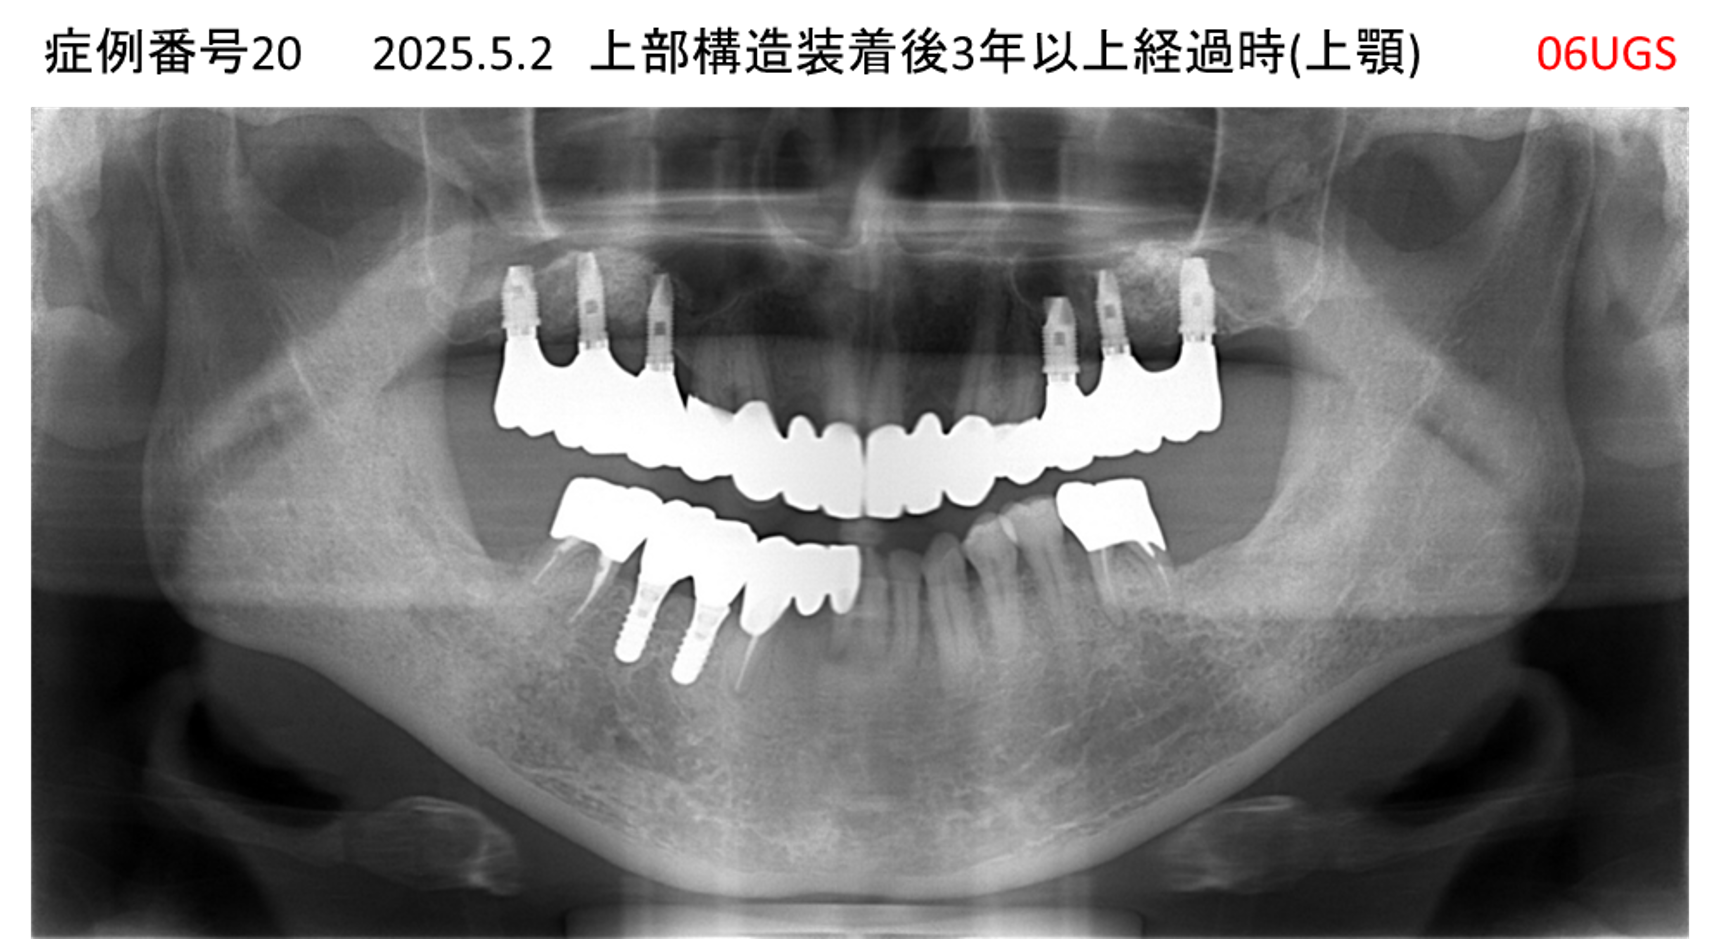

食事ができない/噛めない患者様のインプラント症例

| 治療名称 |

インプラント |

| 治療費用 |

540万円+税 |

| 治療期間 |

6か月 |

| 患者さんの症状(主訴) |

食事ができない。噛めない。上の前歯が揺れてきた。入れ歯がつらい。 |

| 治療内容 |

サイナスリフト、インプラント |

| 治療結果 |

なんでも食べられるようになった。力が入る(全身)ようになった。 |

| 治療の注意点(リスク/副作用) |

インプラントが壊れたら再治療が必要 |